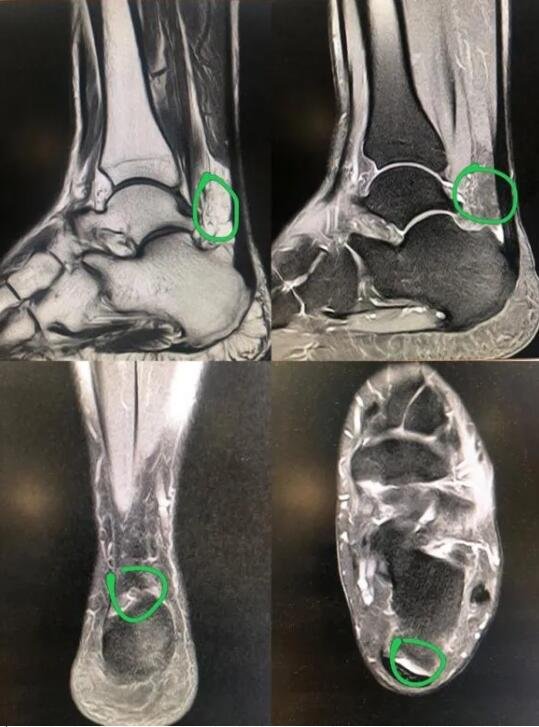

于是来到betway在线登陆足踝外科求诊,接诊的医生检查发现其左跟腱止点处压痛,提踵试验阳性。结合病史体征、辅助检查符合跟腱止点炎诊断。

为更好的保护患者关节,减少创伤,手术团队准备通过踝关节镜行“踝关节镜下清理骨赘切除跟腱止点重建术”。

术中,医生通过踝关节镜下观察病变部位,清理骨赘,切除引起疼痛的跟腱止点,刨刀结合等离子清除增生炎性滑膜。踝关节镜下小骨刀、游离体抓钳清理增生骨赘,并重建跟腱止点,缝合跟腱组织。术中,仅仅2个不足1mm的伤口,在镜下重建跟腱止点,减少创伤。

病变的基础为跟骨后上方的慢性疼痛及骨性增生,并伴有跟腱止点周围炎症,常引起跟骨后疼痛性滑囊炎,并引起相应的疼痛、跛行和足背伸受限的一类疾病。

保守治疗无效患者,可行关节镜下清理、骨突磨削、跟腱支点重建术方式,手术采用跟腱内外入路,对于骨突进行磨削,清理局部滑囊炎,传统手术采取切开清理骨赘重建跟腱止点,创伤大,恢复慢,患者往往需要2-3月恢复时间,并且大的手术切口有感染、切口裂开的风险。我院足踝外科运动医学组常采取关节镜微创技术清理骨赘,镜下重建跟腱止点,帮助患者减少创伤,尽快恢复运动功能。